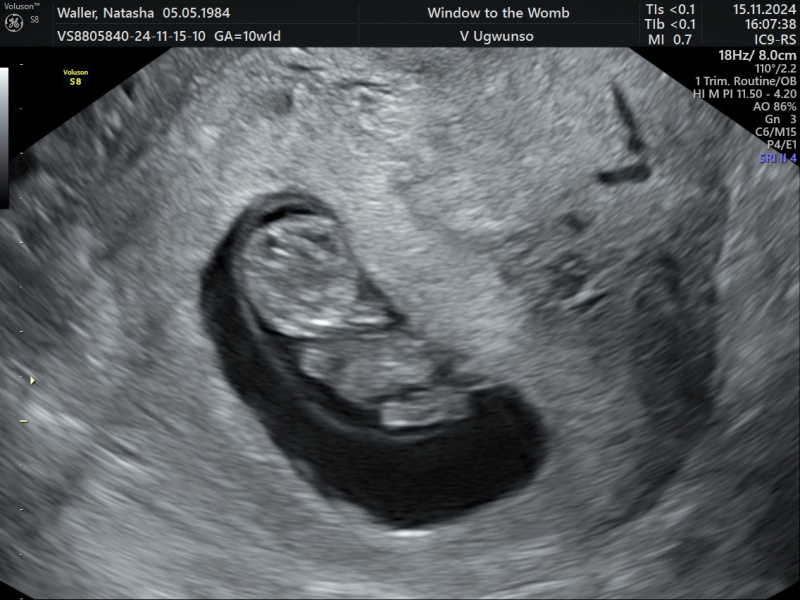

Had my booking in appointment today , midwife said I’ll probably need aspirin as my mum had preeclampsia but I never had it with my other Children and they always knew my mums history. Had a private scan Friday as my dates were off when I had an early scan at EPU , they have caught up now I’m 10 weeks today due 15th June but I’ll be nearly 14 weeks when i have my 12 week scan now ! Midwife said ring to bring it forward. Booked in for Nipt on Friday. Here’s a pic of prawny who looks a lot less prawn like now 🤣 hope everyone is doing ok x

@38startingagain lovely scan pic.

@38startingagain Congratulations - prawny is looking wonderful! Confusing re the dates but at least your 12 week will be sooner!

@38startingagain What a gorgeous picture! Good luck for the NIPT. Does anyone know how much blood they take?